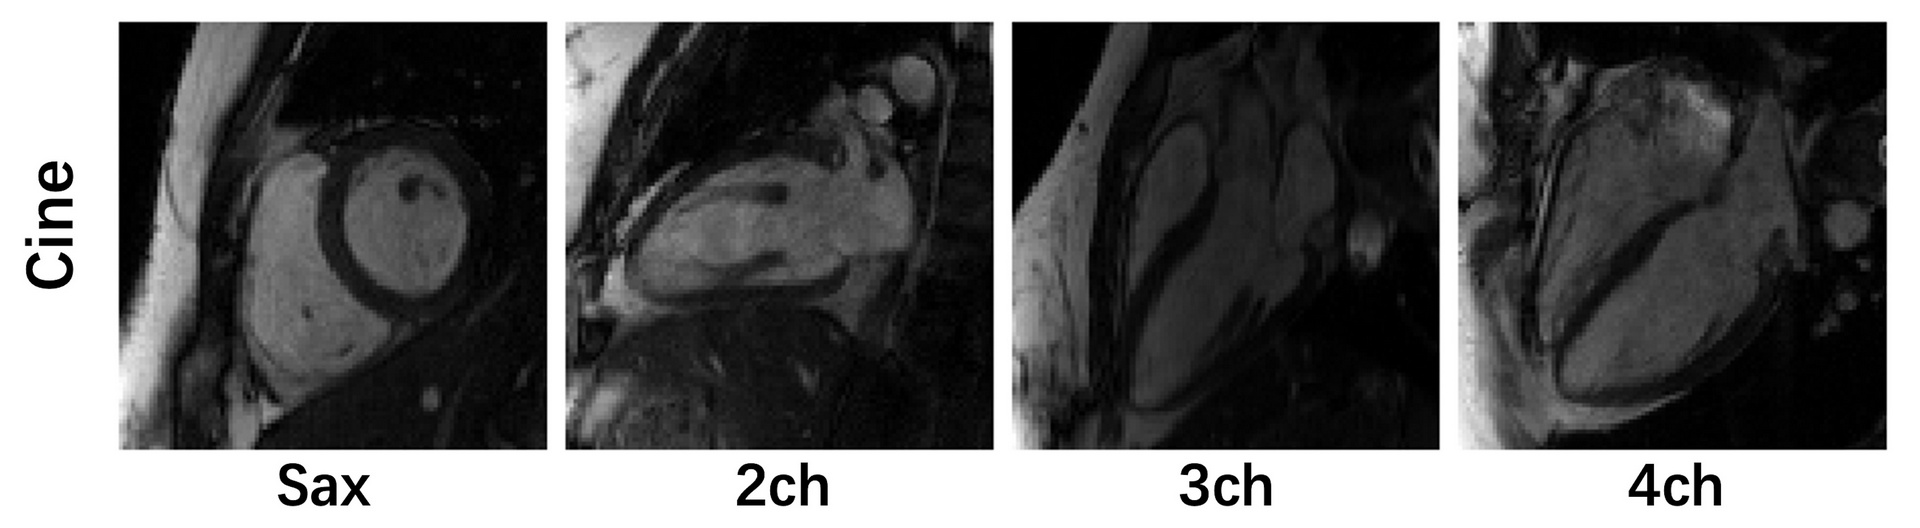

Image acquisition:  We followed the recommendations of CMR imaging reported in the previous publication ( d oi: 10.1007/s43657-02100018x, 10.1007/s43657-021-00018-x [w.c.y.1] ). The ‘TrueFISP’ readout was used for CINE acquisition. The collected images include short-axis (SA), two-chamber (2CH), three-chamber (3CH) and four-chamber(4CH) long-axis (LA) views. Typically 5~10 slices were acquired for  SA cine, while a single slice was acquired for the other views. The cardiac cycle was segmented into 12–25 phases with a temporal resolution 50 ms. For this challenge, we provided raw k-space data of both SA (multi-slices) and LA (multi-views). Typical scan parameters: spatial resolution 2.0×2.0 mm2, slice thickness 8.0 mm, and slice gap 4.0 mm.